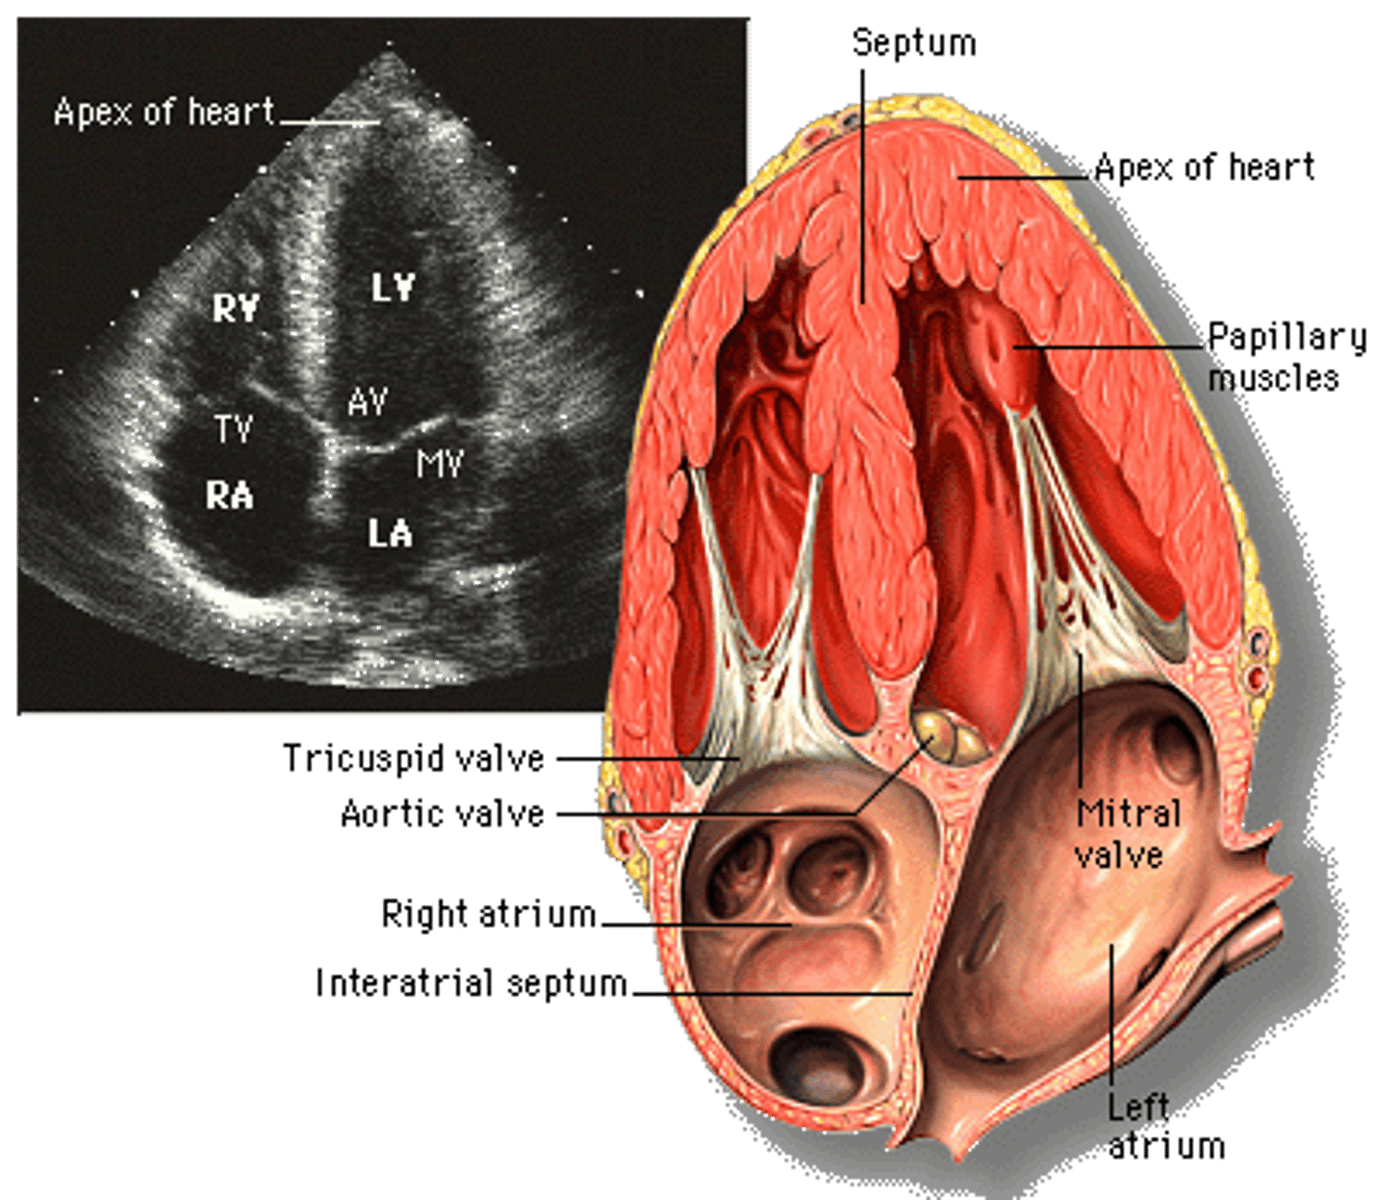

What is apical view?

transducer located over apex, giving a 4CH view

Label the fetal heart